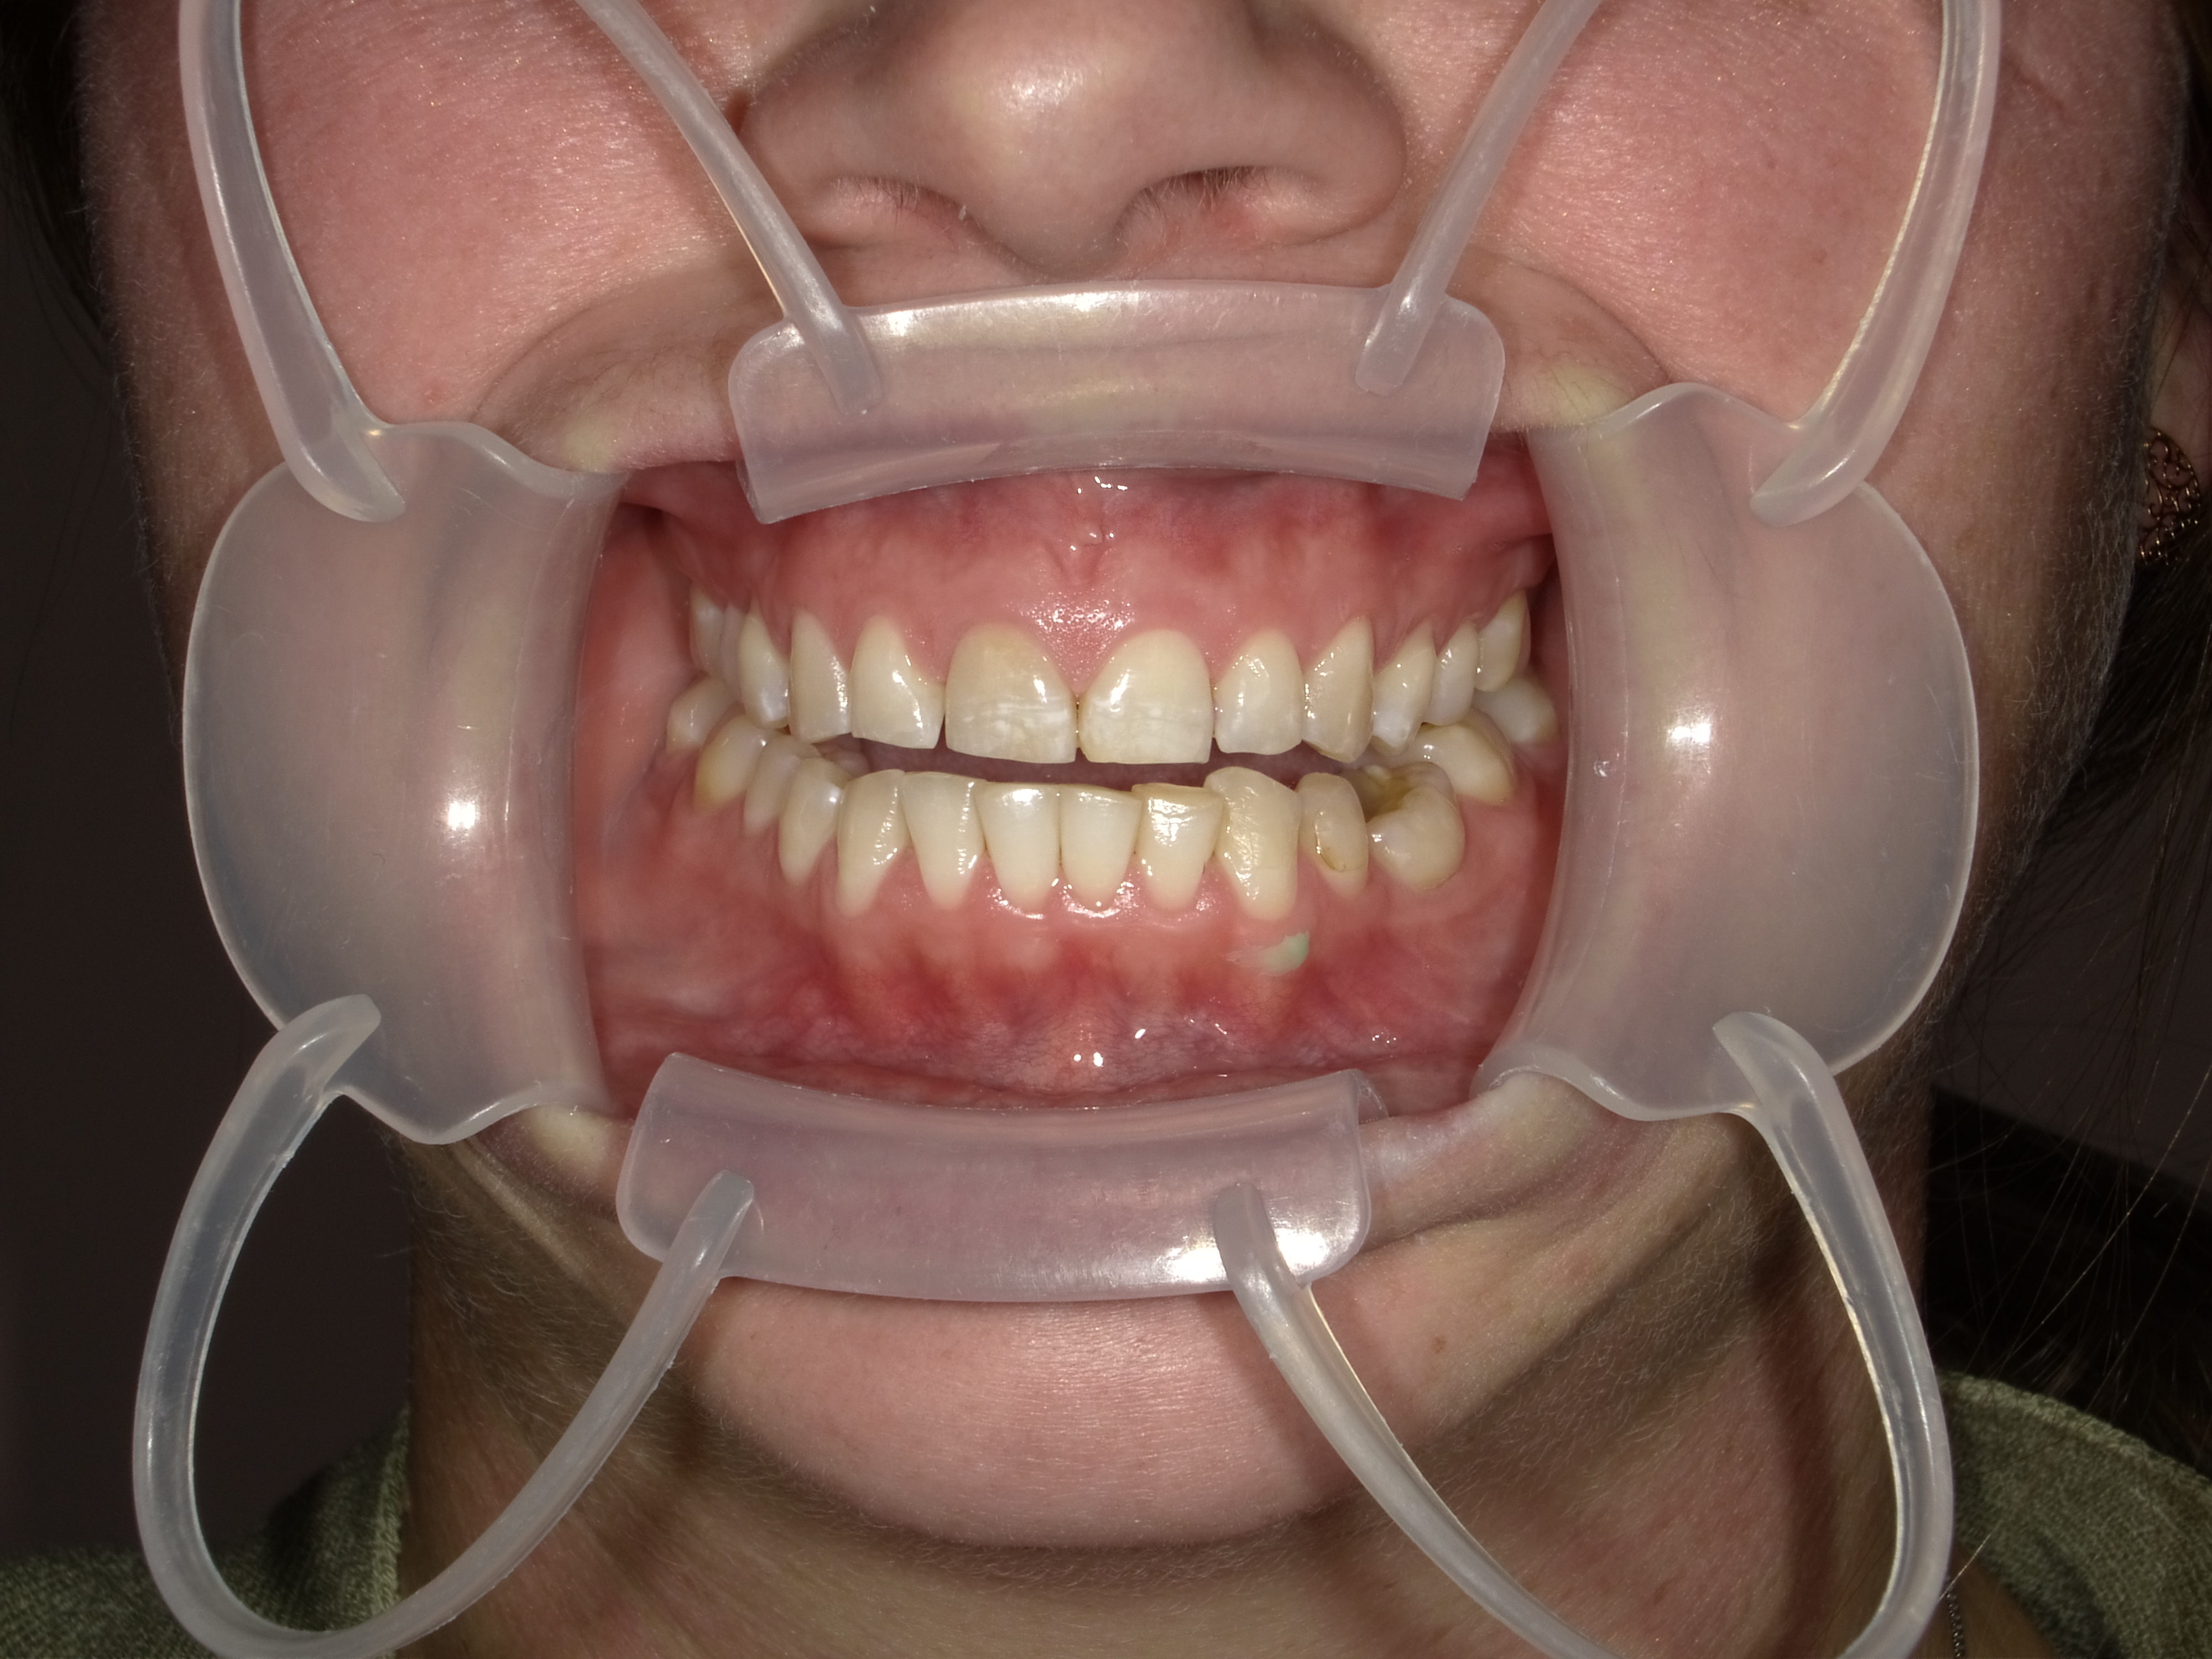

Patient Photographs

At a minimum, 4 photos are required.

1. Front view smile not retracted

2. Front view retracted

3. Maxilary retracted (with mirror is best.

4. Mandibular retracted.

Good lighting is key. A cell phone can be used with flash.

Placeholder Picture